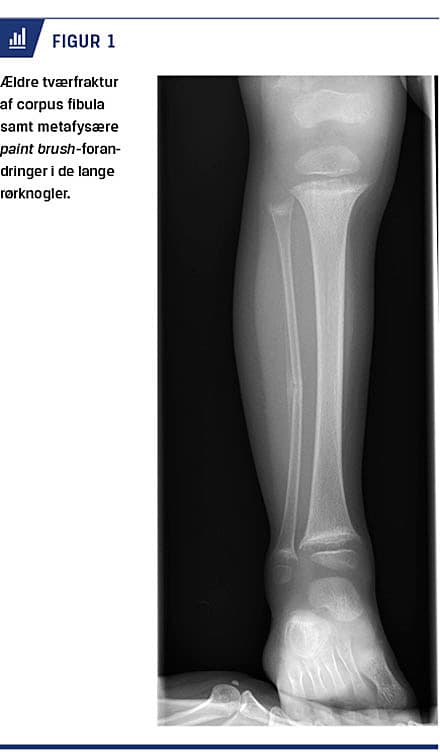

En røntgenoptagelse af højre crus viste tværfraktur af corpus fibula med periostal reaktion, hvilket tydede på en fraktur af ældre dato. Der var paint brush-forandringer metafysært i samtlige medfotograferede lange rørknogler, hvilket mest sandsynligt repræsenterede rakitisforandringer (Figur 1). Blodprøver viste meget lavt D-vitaminniveau (8 nmol/l), massivt forhøjet parathyroideahormonniveau (99,7 pmol/l), umåleligt højt basisk fosfatase-niveau (> 1.200 E/l), diskret nedsat ioniseret calciumniveau (2,16 mmol/l) og moderat nedsat fosfatniveau (0,49 mmol/l). Dertil mikrocytær anæmi med lavt hæmoglobinniveau (4,5 mmol/l) og lavt middelcellevolumen (60 fl). Desuden fandt man lavt ferritinniveau (3 mikrog/l) og normalt reticulocytniveau (62 × 109/l). Infektionstal, nyretal og øvrige levertal var normale.